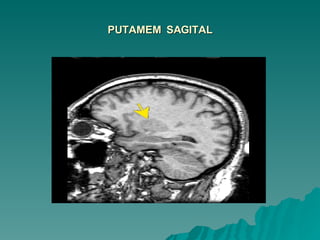

PUTAMEM  SAGITAL